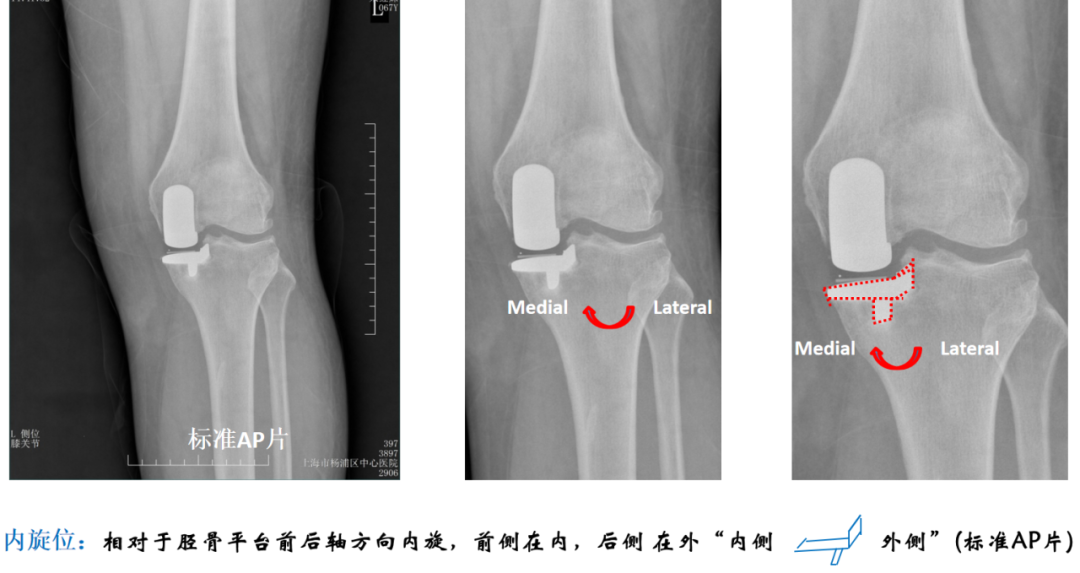

病例1

术后X-ray:正位片内旋,显示胫骨假体大小及位置佳(垂直截骨在棘突顶点、与内侧缘齐平、无内外翻)。

病例2

术后X-ray:标准正位片,显示胫骨假体大小及位置佳(垂直截骨在棘突顶点、与内侧缘齐平、无内外翻)。